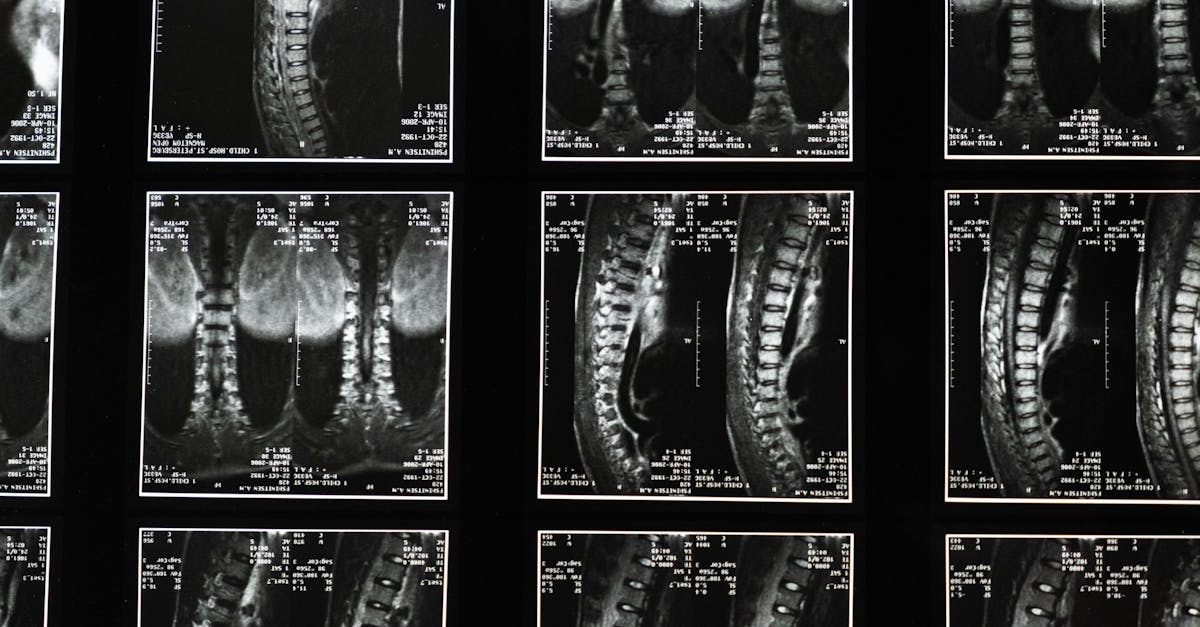

La décompression neurovertébrale consiste en une technique douce qui utilise une traction contrôlée sur la colonne vertébrale. Cette approche vise à augmenter l’espace entre les vertèbres, permettant ainsi de diminuer la pression sur les nerfs et de favoriser une meilleure circulation sanguine. Cela aide à réduire la douleur et à promouvoir la guérison des tissus environnants.

La décompression neurovertébrale se manifeste comme une technique innovante qui répond aux besoins des patients souffrant de douleurs neuropathiques chroniques. Cette approche non invasive vise à soulager les douleurs de la colonne vertébrale sans recourir à des interventions chirurgicales. Grâce à des méthodes de traction douce, la décompression neurovertébrale permet de réduire la pression exercée sur les disques intervertébraux et les nerfs, offrant ainsi une alternative appréciée par de nombreux patients. En réduisant ces tensions, elle favorise la circulation sanguine et contribue à un état de bien-être général.

La méthode repose sur des principes biomécaniques qui utilisent des équipements modernes pour assurer un traitement précis et contrôlé. En intégrant des technologies avancées telles que la thérapie au laser et la thérapie par ondes de choc, la décompression neurovertébrale améliore les résultats cliniques tout en minimisant les effets secondaires indésirables. Ainsi, la nécessité d’anesthésie est évitée, rendant le traitement plus accessible et rassurant pour les patients.

En alternative aux traitements invasifs et aux médicaments, la décompression neurovertébrale propose une approche douce qui respecte le corps tout en ciblant les causes profondes des douleurs. Cette méthode, fondée sur des principes biomécaniques et utilisant des techniques de traction contrôlée, favorise non seulement la réduction de la douleur, mais aussi une amélioration globale de la mobilité des patients. Ce processus contribue également à améliorer la circulation sanguine, apportant ainsi des bénéfices nutritionnels essentiels pour la santé des disques intervertébraux.